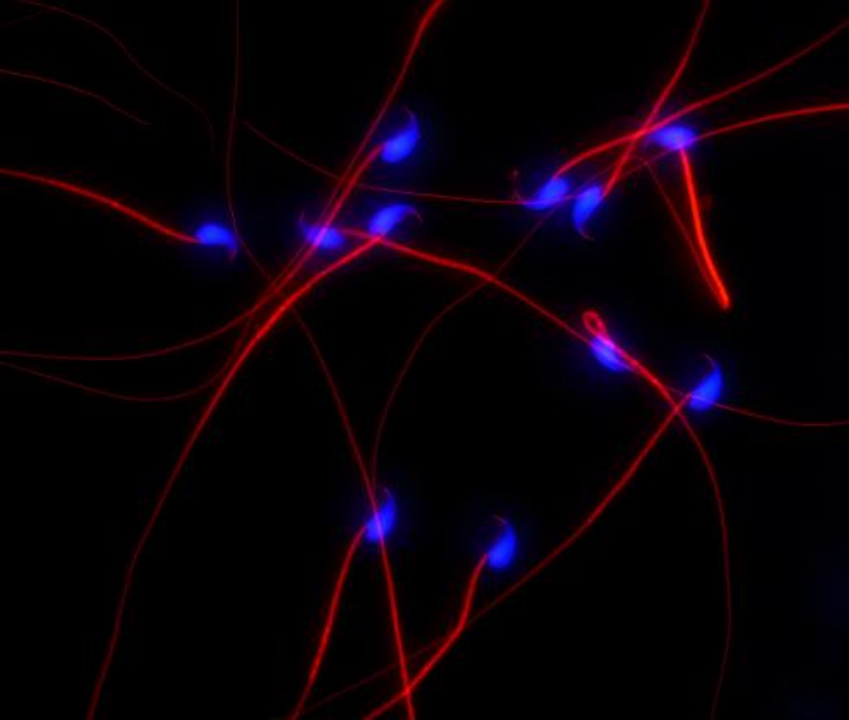

《一段浓蓝一段红》

熊雨平 (基础医学与法医学院 2022级基础医学专业研究生)

本图为小鼠精子细胞荧光染色图,蓝色是精子头部,红色是精子尾部。蓝色和红色,彼此交织在一起构成完整形态的精子细胞,形成了生命之初的绚丽景象。